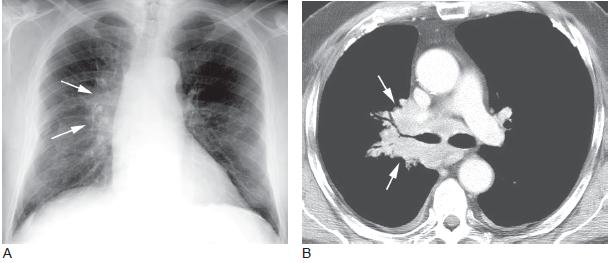

肺癌晚期 胸片

肺癌晚期 胸片,肺癌胸片晚期

肺癌的影像学表现【下】(多图)

肺癌胸片晚期

肺癌胸片

中央型肺癌胸片

肺癌ct图片

肺癌ct图片图解

肺癌CT